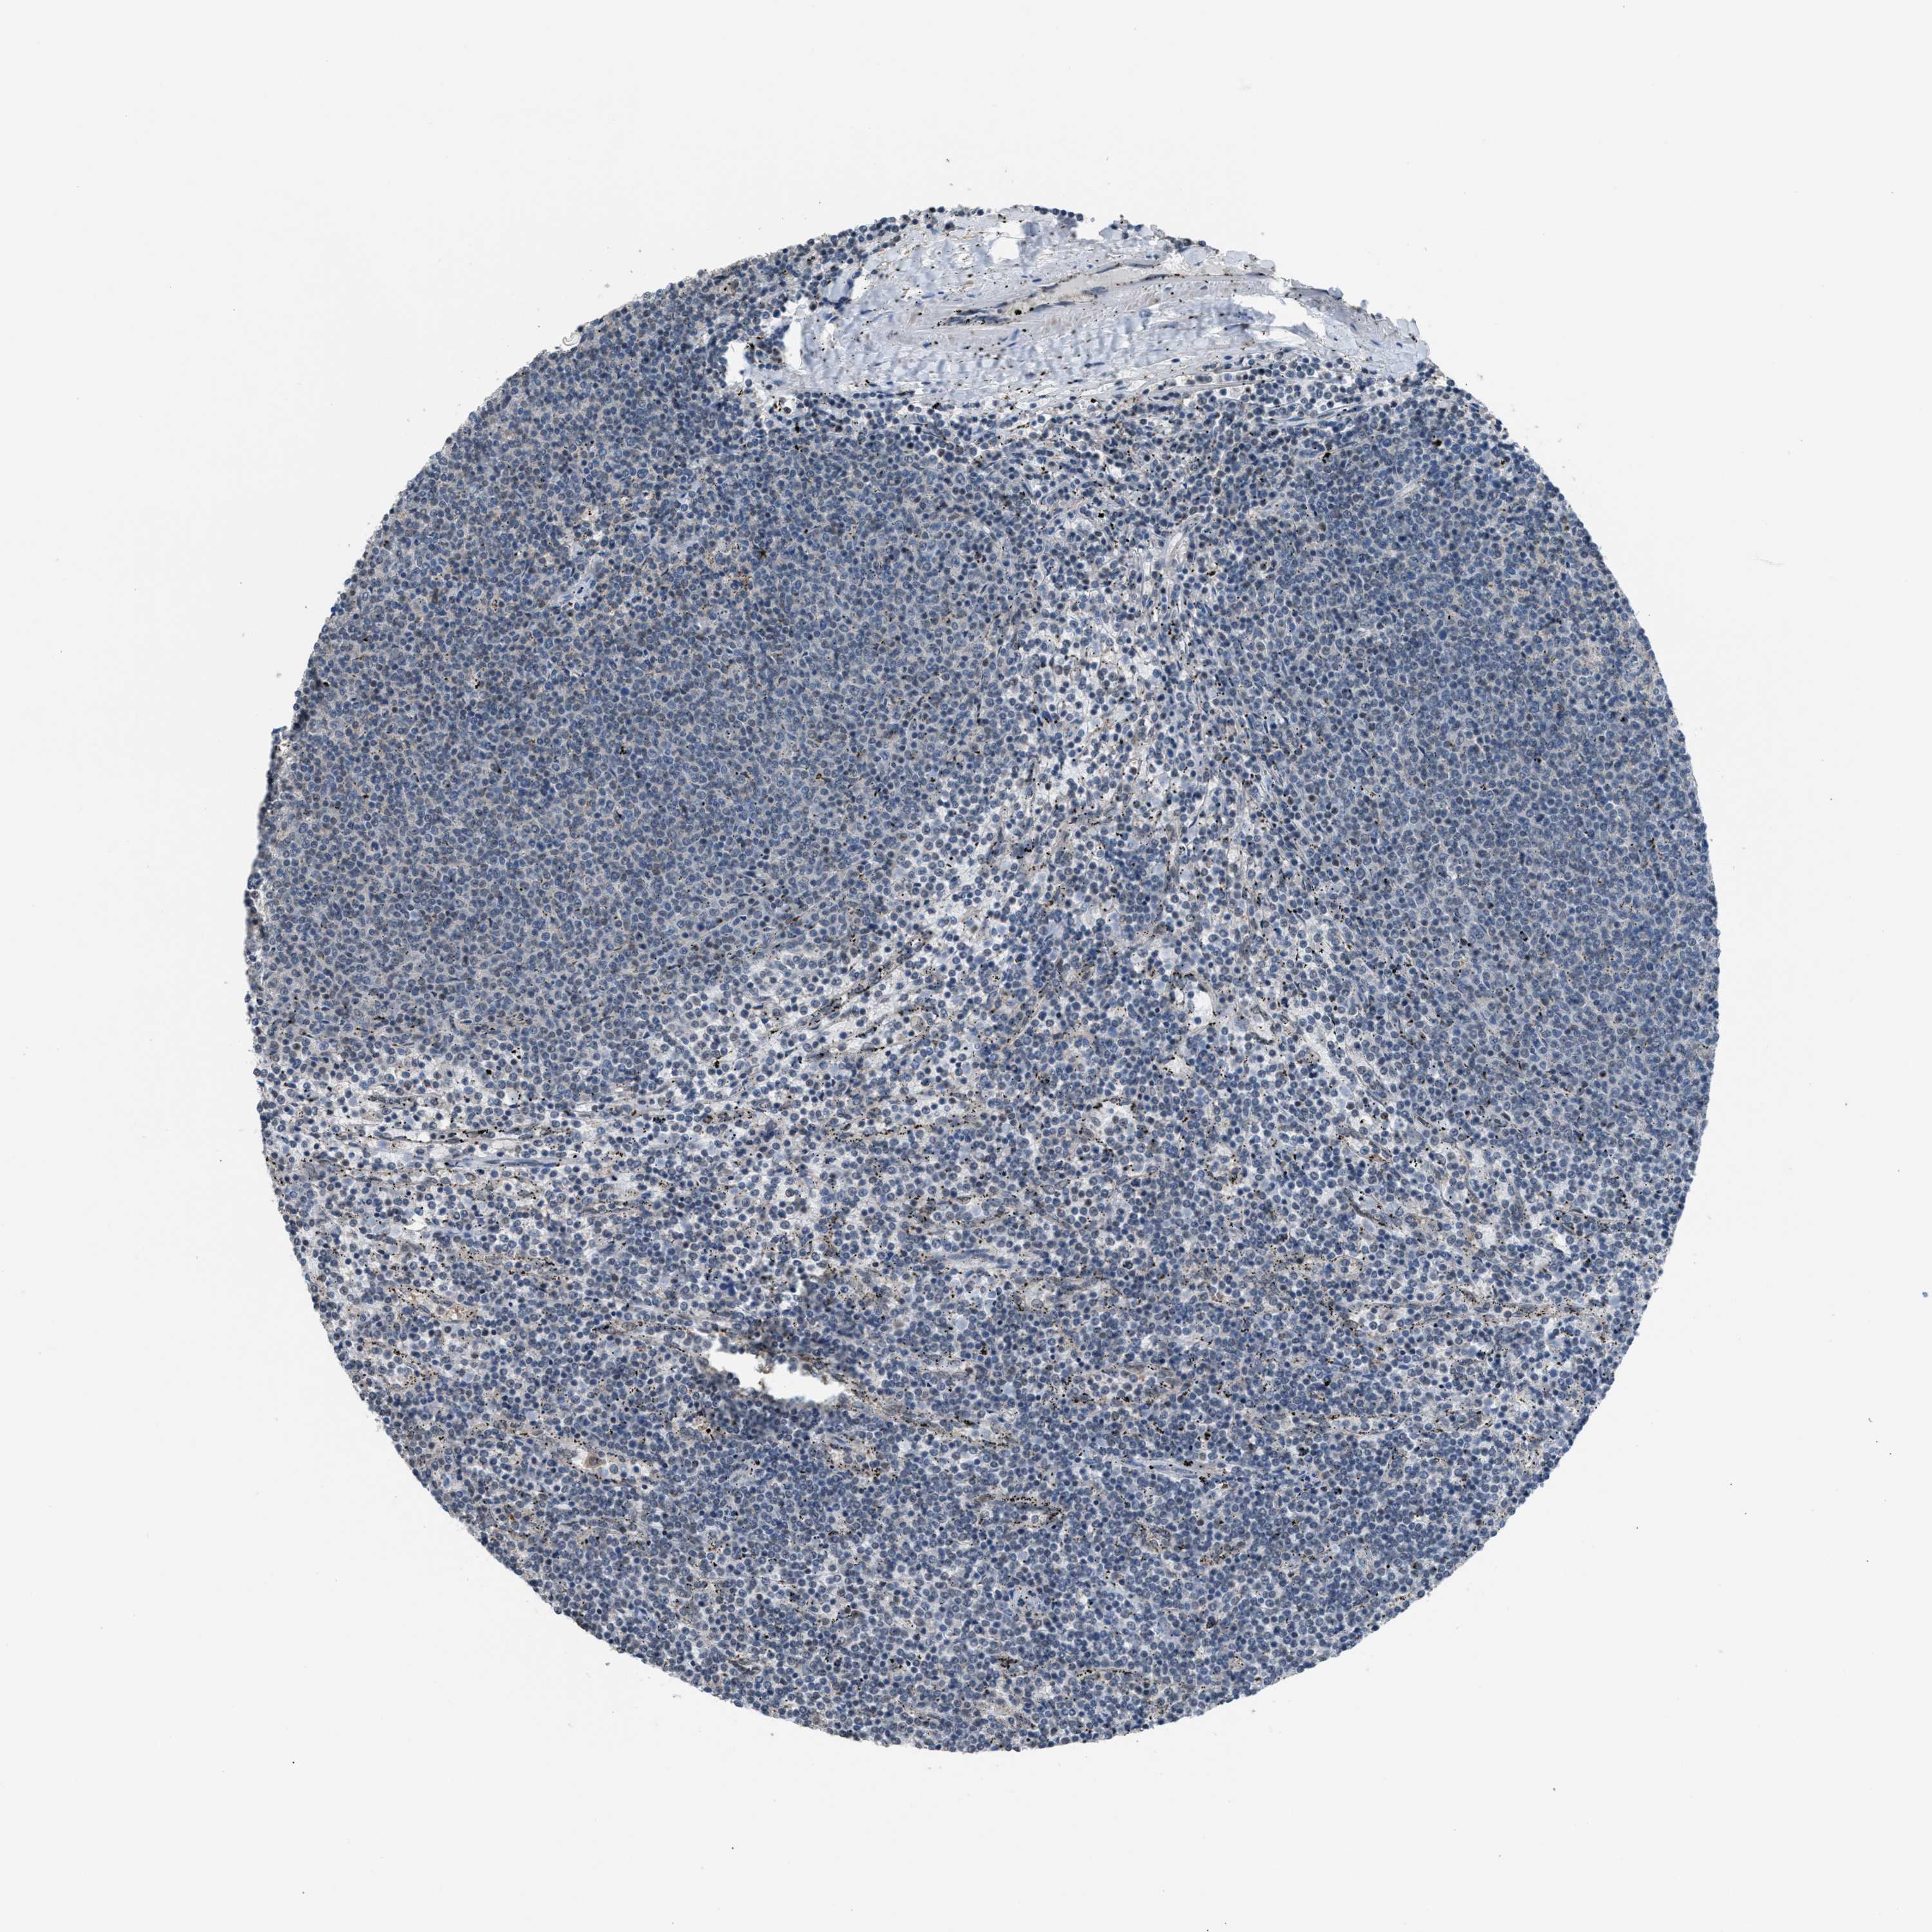

LYMPHOMA - Protein expressioni

A mouse-over function shows sample information and annotation data. Click on an image to view it in a full screen mode. Samples can be filtered based on level of antibody staining by selecting one or several of the following categories: high, medium, low and not detected. The assay and annotation is described here.

Antibody stainingi

Antibody staining in the annotated cell types in the current human tissue is reported as not detected, low, medium, or high, based on conventional immunohistochemistry profiling in selected tissues. This score is based on the combination of the staining intensity and fraction of stained cells.

Each image is clickable and will lead to virtual microscopy that enables deeper exploration of all samples and also displays staining intensity scores, fraction scores and subcellular localization as well as patient and tissue information for each sample.

Antibody HPA021309

Antibody HPA022255

Staining

High

Medium

Low

Not detected

Intensity

Strong

Moderate

Weak

Negative

Quantity

>75%

75%-25%

<25%

None

Location

Nuclear

Cytoplasmic/membranous

Cytoplasmic/membranous,nuclear

Hodgkin's disease, NOS

Malignant lymphoma, non-Hodgkin's type, High grade

Malignant lymphoma, non-Hodgkin's type, Low grade